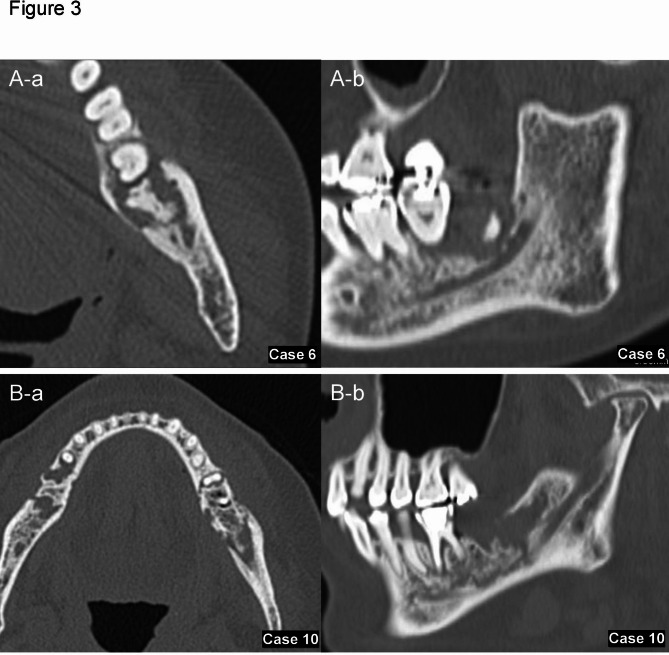

Objectives: Microbial infections can influence destructive jawbone lesions, yet the role of Entamoeba gingivalis (E. gingivalis) in these lesions is poorly understood, particularly when co-infected with Actinomyces. This study introduces a novel clinicopathological perspective on jawbone destruction linked to E. gingivalis and Actinomyces co-infection, aiming to improve diagnosis and treatment. In this study, we tried to evaluate minimally invasive methods for improving diagnosis and treatment for jawbone destruction, possibly linked to E. gingivalis and Actinomyces co-infection. We analyzed 11 cases of jawbone destructive lesions observed in patients (ages 42 to 83, both female and male) who visited Tohoku University Hospital from January 2015 to December 2021, in which scraping cytology detected E. gingivalis and Actinomyces.

Materials and methods: We thoroughly assessed clinical symptoms, imaging findings, and treatment outcomes, including the duration of antimicrobial therapy, to identify distinctive patterns associated with this co-infection.

Results: On imaging, patients exhibited significant mandibular resorption and sclerosis, despite the absence of typical symptoms of osteomyelitis or actinomycosis. Notably, E. gingivalis alone was linked to faster wound healing and shorter antimicrobial therapy durations compared to cases with concurrent Actinomyces infection (p = 0.011). The use of minimally invasive procedures, focusing on removing necrotic bone and loose teeth, led to effective healing and rapid recovery across all cases, offering promising prospects for enhanced treatment outcomes.